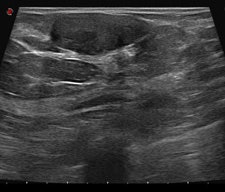

After detection of a possible lesion using a front-line method such as standard two-view mammography, additional techniques should be used if there is reasonable suspicion of cancer. Superimposed breast tissue can mimic a malignant lesion. If the lesion exists, other techniques can help the radiologist to decide about the degree of concern and to classify the lesion correctly. These were discussed during Friday's session. In addition, speakers covered the influence of clinical data on classification.